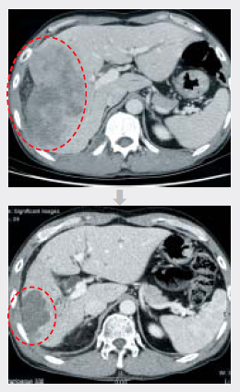

°£ ¿À¸¥ÂÊ¿¡ 11§¯ Å©±âÀÇ ¾ÏÀÌ ÀÖ´Â º¹ºÎCT»çÁø(À§)°ú ±¹¼ÒÀûÇ׾Ϲæ»ç¼±µ¿½Ã¿ä¹ýÀ» ÇÏ°í ³­ µÚ ¾Ï Å©±â°¡ 6.8§¯·Î ÁÙ¾îµç ¸ð½À.

°£ ¿À¸¥ÂÊ¿¡ 11§¯ Å©±âÀÇ ¾ÏÀÌ ÀÖ´Â º¹ºÎCT»çÁø(À§)°ú ±¹¼ÒÀûÇ׾Ϲæ»ç¼±µ¿½Ã¿ä¹ýÀ» ÇÏ°í ³­ µÚ ¾Ï Å©±â°¡ 6.8§¯·Î ÁÙ¾îµç ¸ð½À. / ¿¬¼¼¾Ïº´¿ø °£¾Ï¼¾ÅÍ Á¦°ø

°íµîÇб³ ±³»ç ±è¸ð(45)¾¾´Â 2005³â °£¾Ï Áø´ÜÀ» ¹Þ¾Ò´Ù. °£ ¿À¸¥ÂÊ¿¡ 11§¯ Å©±âÀÇ ¾ÏÀÌ ÀÖ¾ú°í °£À» Áö³ª´Â Ç÷°ü¿¡µµ ¾ÏÀÌ Ä§¹üÇÑ »óÅ¿´´Ù. ¾ÏÀÌ °£ÀÇ Àý¹Ý ÀÌ»óÀ» Â÷ÁöÇϰí ÀÖ¾î ¼ö¼úÀÌ ¾î·Á¿ü´Ù. ´ç½Ã ÁÖÄ¡ÀÇ¿´´ø ¿¬¼¼¾Ïº´¿ø °£¾Ï¼¾ÅÍ Çѱ¤Çù ±³¼ö´Â °£µ¿¸Æ¿¡ Ç×¾ÏÁ¦¸¦ ÁÖÀÔÇϰí, ¹æ»ç¼± Ä¡·á¸¦ º´ÇàÇÏ´Â '±¹¼ÒÀûÇ׾Ϲæ»ç¼±µ¿½Ã¿ä¹ý(CCRT)'À» ±ÇÇß´Ù. ½Ã¼ú ÈÄ ¾ÏÀÇ Å©±â°¡ 11§¯¿¡¼­ 6.8§¯·Î ÁÙ¾îµç ´öºÐ¿¡ ±è¾¾´Â ¾Ï¼¼Æ÷¸¦ ÀýÁ¦ÇÏ´Â ¼ö¼úÀ» ¹Þ¾Ò´Ù. ±è¾¾´Â 8³âÀÌ Áö³­ Áö±Ýµµ °Ç°­ÇÏ´Ù.